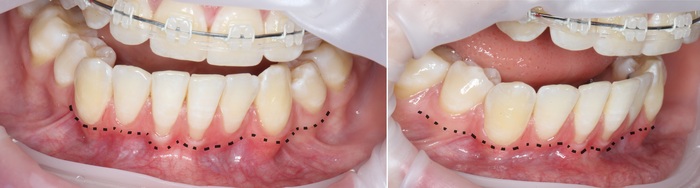

2 – проведение пластики десны.

Был взят трансплантат в области бугра верхней челюсти (это то место, где раньше был зуб мудрости).

Далее проведена пластика десны, снова два месяца ожиданий и установка временной коронки: